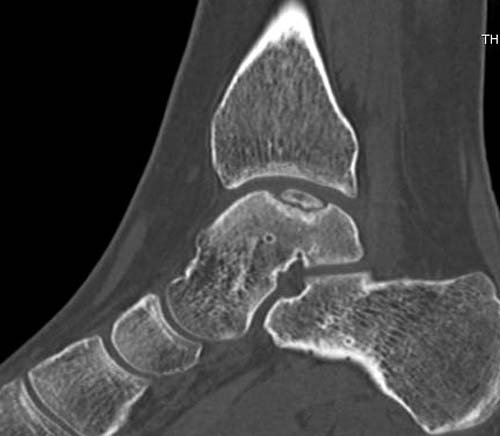

Доброго времени суток, уважаемые коллеги. Прошу помочь определиться с тактикой лечения. Пациентка 40 лет, в течение последних 8-9 мес. беспокоила боль в левом голеностопном суставе после значительной физической нагрузки (по роду деятельности вынуждена проходить в день не менее 15 км). Факт травмы отрицает. Лечилась самостоятельно, мазями и приемом НПВП. В последнее время боль стала возникать после умеренной нагрузки, присоединились отек и хромота. Прием НПВП и ограничение нагрузки до уровня бытовой болевой и отечный синдром купируют. Обратилась к нам, выявлены изменения таранной и пяточной кости, представленные на КТ. Вопрос: единственным ли выходом является артродез или можно обойтись менее радикальным вмешательством? Смущает невыраженная клиника и молодой возраст пациентки... Будем рады любой помощи со стороны уважаемого сообщества. А. Баженов, г. Екатеринбург

Разбираемый случай не имеет ничего общего с классическим Аваскулярным Некрозом Таранной кости. Здесь так назывемый (osteochondral defect) или osteochondritis dissecans (OCD) таранной кости, при котором патология локализуется в медиально-верхнем нагрузочном отделе. В основном OCD

встречается после хронической травмы, но бывают случаи врожденного генеза, которые обнаруживаются при случайных исследованиях.

на рентгенограммах не всегда заметны склерозные участки, и поэтому в большинстве диагноз устанавливается поздно. Приход КТ и МРТ улучшил диагностику, и в срезах внутри кисты можно увидеть жидкость, но это не означает проявление симптоматологии. Симптомы проявляются с момента образования внутрисуставных краевых фрагментаций!

Сравнивал представленные КТ с тем что есть в сети в свободном доступе - тоже не нашел разницы между OCD и AVN таранной кости